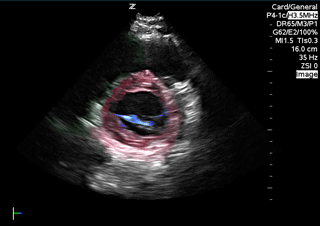

Parasternal short axis Red: Left ventricle, Blue: Mitral valve, Green: Right ventricle Images: Dr. Lindsay Davis, Dr. Hannah Kopinski. Image Editing: Michael Amador and Dr. Matthew Riscinti